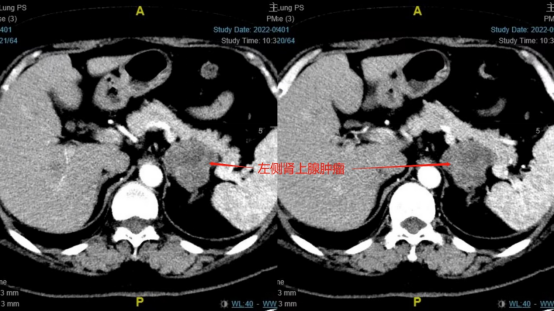

胡先生(化名)今年46岁,血压一直控制不佳,口服硝苯地平片、美托洛尔缓释片等药物控制6年,半年前还曾因为血压骤升而导致脑梗死。半月前胡先生血压在200/100–150/80mmHg左右频繁波动,致使头痛、头晕反复发作。在当地医院行肾上腺CT检查发现:左侧腹膜后一大小约6*5*3.5cm肿物。入院完善检查检验后初步诊断为左侧异位嗜铬细胞瘤。行机器人辅助腹腔镜下左侧腹膜后肿物切除术,术后病理回报:左侧腹膜后肿物,6*5*3.5cm灰黄色结节,包膜完整,诊断为嗜铬细胞瘤/副神经节瘤。

病历二肾上腺256增强CT图